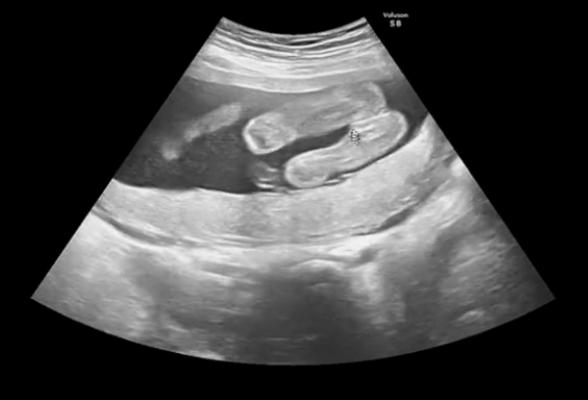

先日の検診にて、性別は女の子で間違いないだろうと先生から言われました。

エコーでもお尻側から見たのですが、これは本当に女の子確定で良いのでしょうか??

先生がおっしゃっていたように、お股のところに割れ目が映っている様に見えますので、女の子になるのかなと思いました。(お股に挟んで隠していることがなければ。この映っている割れ目は、女の子のシンボルとされることもあります)

こちらでは診断をする事はできませんので、はっきりとした事は分かりませんが、そのようには思いました。